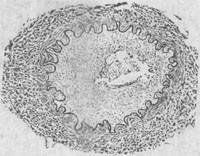

1.急性型 此型以敗血症、全身性黃疸和各器官、組織廣泛性出血以及壞死為主要特徵。皮膚、皮下組織、漿膜和可視黏膜、肝臟、腎臟以及膀胱等組織黃染和不同程度的出血。皮膚乾燥和壞死。胸腔及心包內有渾濁的黃色積液。脾臟腫大、淤血,有時可見出血性梗死。肝臟腫大,呈土黃色或棕色,質脆,膽囊充盈、淤血,被膜下可見出血灶。腎臟腫大、淤血、出血。肺淤血、水腫,表面有出血點。膀胱積有紅色或深黃色尿液。腸及腸系膜充血,腸系膜淋巴結、腹股溝淋巴結、頜下淋巴結腫大,呈灰白色。